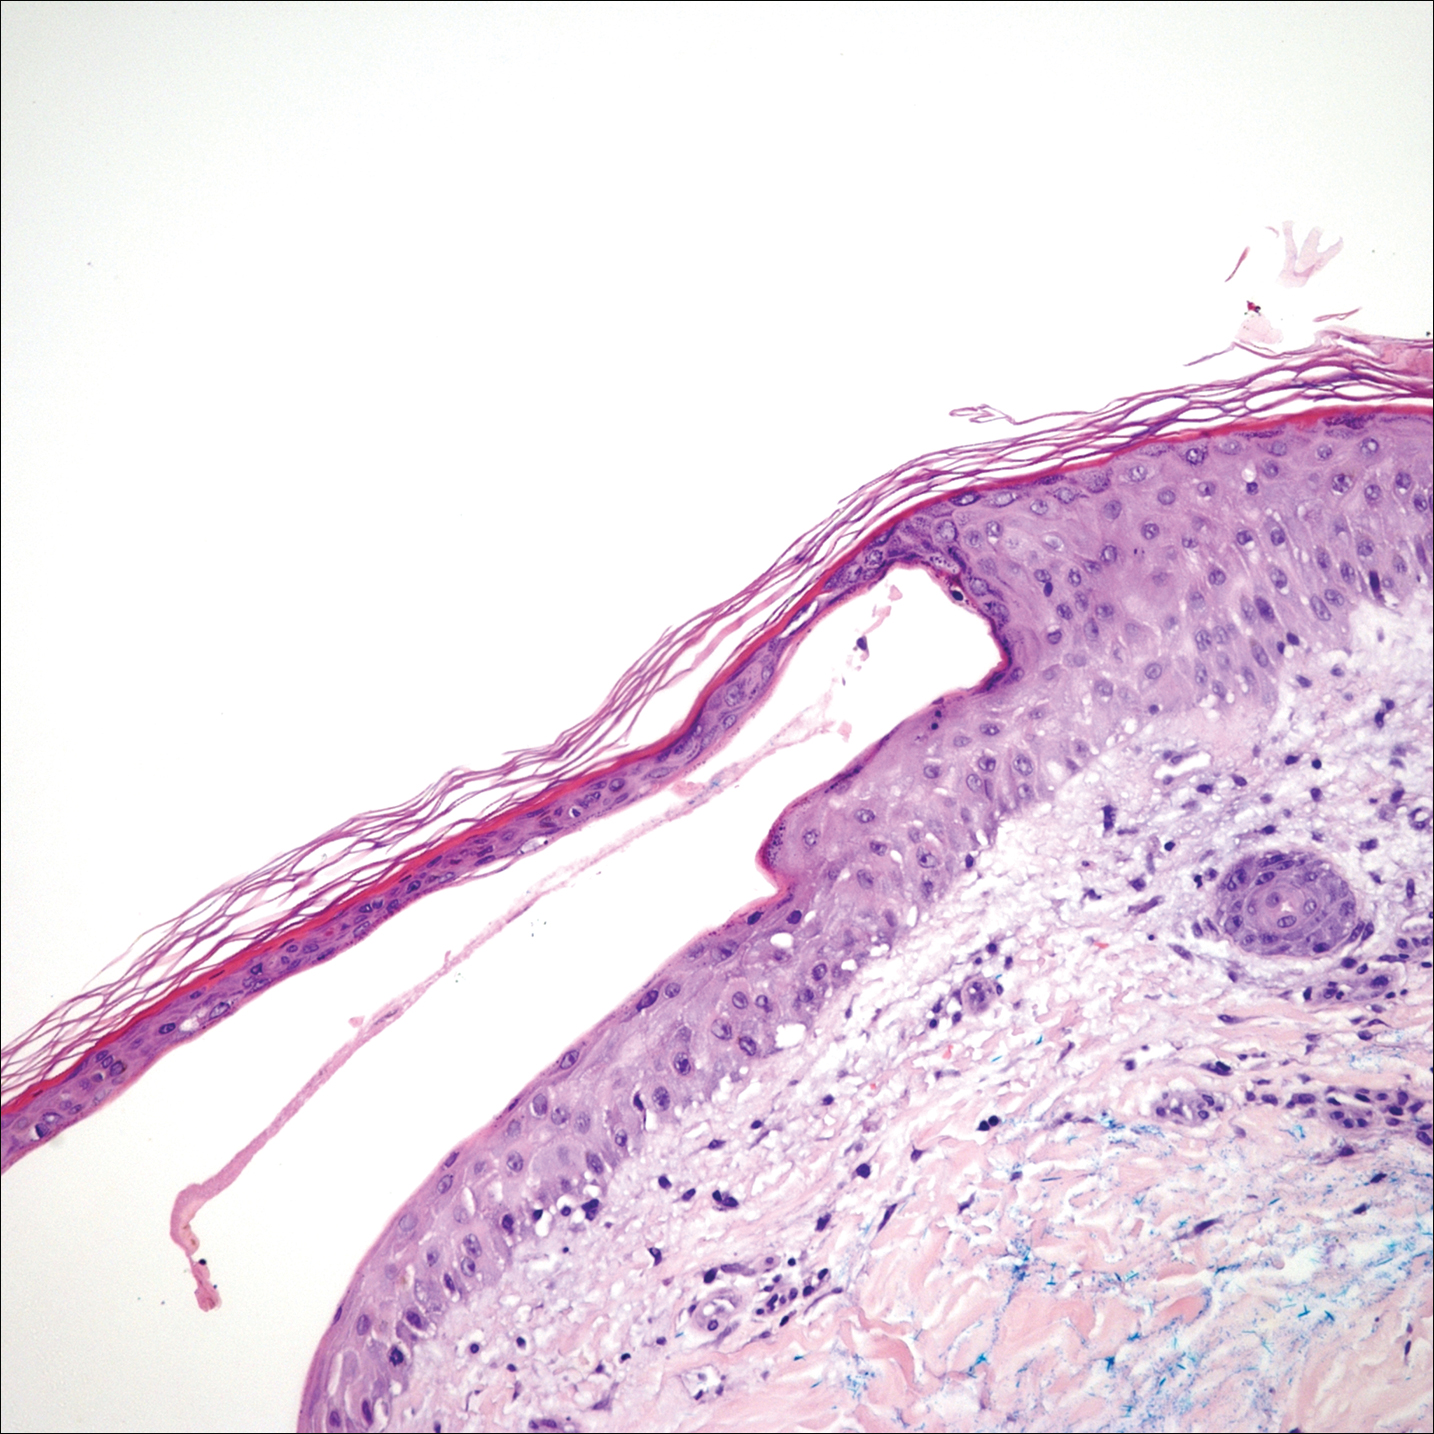

The shave biopsy pathology demonstrated a subepidermal bulla with re-epithelialization that was clinically consistent with fracture blisters (also known as fracture bullae)(Figure). Fracture blisters are a complication of bone fractures, usually occurring 24 to 48 hours after the trauma but possibly up to 3 weeks later. The skin usually is edematous with tense bullae overlying the fracture (in this case it was distal to the fracture); most blisters contain clear fluid, but older blisters tend to be more flaccid with hemorrhagic fluid.1 The cause is thought to be the result of skin strain during fracture formation.2 Edema and hypoxia from injured vessels and lymphatics contribute to the formation of bullae, which are seen as a dermoepidermal junction split on histology.1

The bullae are histologically indistinguishable from edema blisters. A clinical history can help to differentiate. Edema blisters occur in the setting of an acute exacerbation of chronic edema, usually on the lower extremities in the setting of fluid overload.3 Bullous cellulitis is associated with skin erythema, warmth, and systemic symptoms. Bullous pemphigoid can be localized to the lower legs at times; however, biopsy would show a subepidermal bulla with eosinophils along the dermoepidermal junction. Linear IgA bullous dermatosis can be drug induced from vancomycin; however, pathology would show a subepidermal blister with a neutrophil predominant infiltrate. Nonsteroidal anti-inflammatory medications such as naproxen are a common culprit for bullous drug eruptions, which can be localized or generalized and include diagnoses such as fixed drug eruption, toxic epidermal necrolysis, and drug-induced pseudoporphyria. Naproxen-induced pseudoporphyria more commonly presents with blisters, erosions, and scarring with a predilection for the dorsal hands. Histology also will demonstrate subepidermal bullae. Clues to differentiate pseudoporphyria from fracture blisters include festooning of the dermal papilla and caterpillar bodies consisting of basement membrane material and colloid bodies in the basal layer of the epidermis, though they are not always present.4